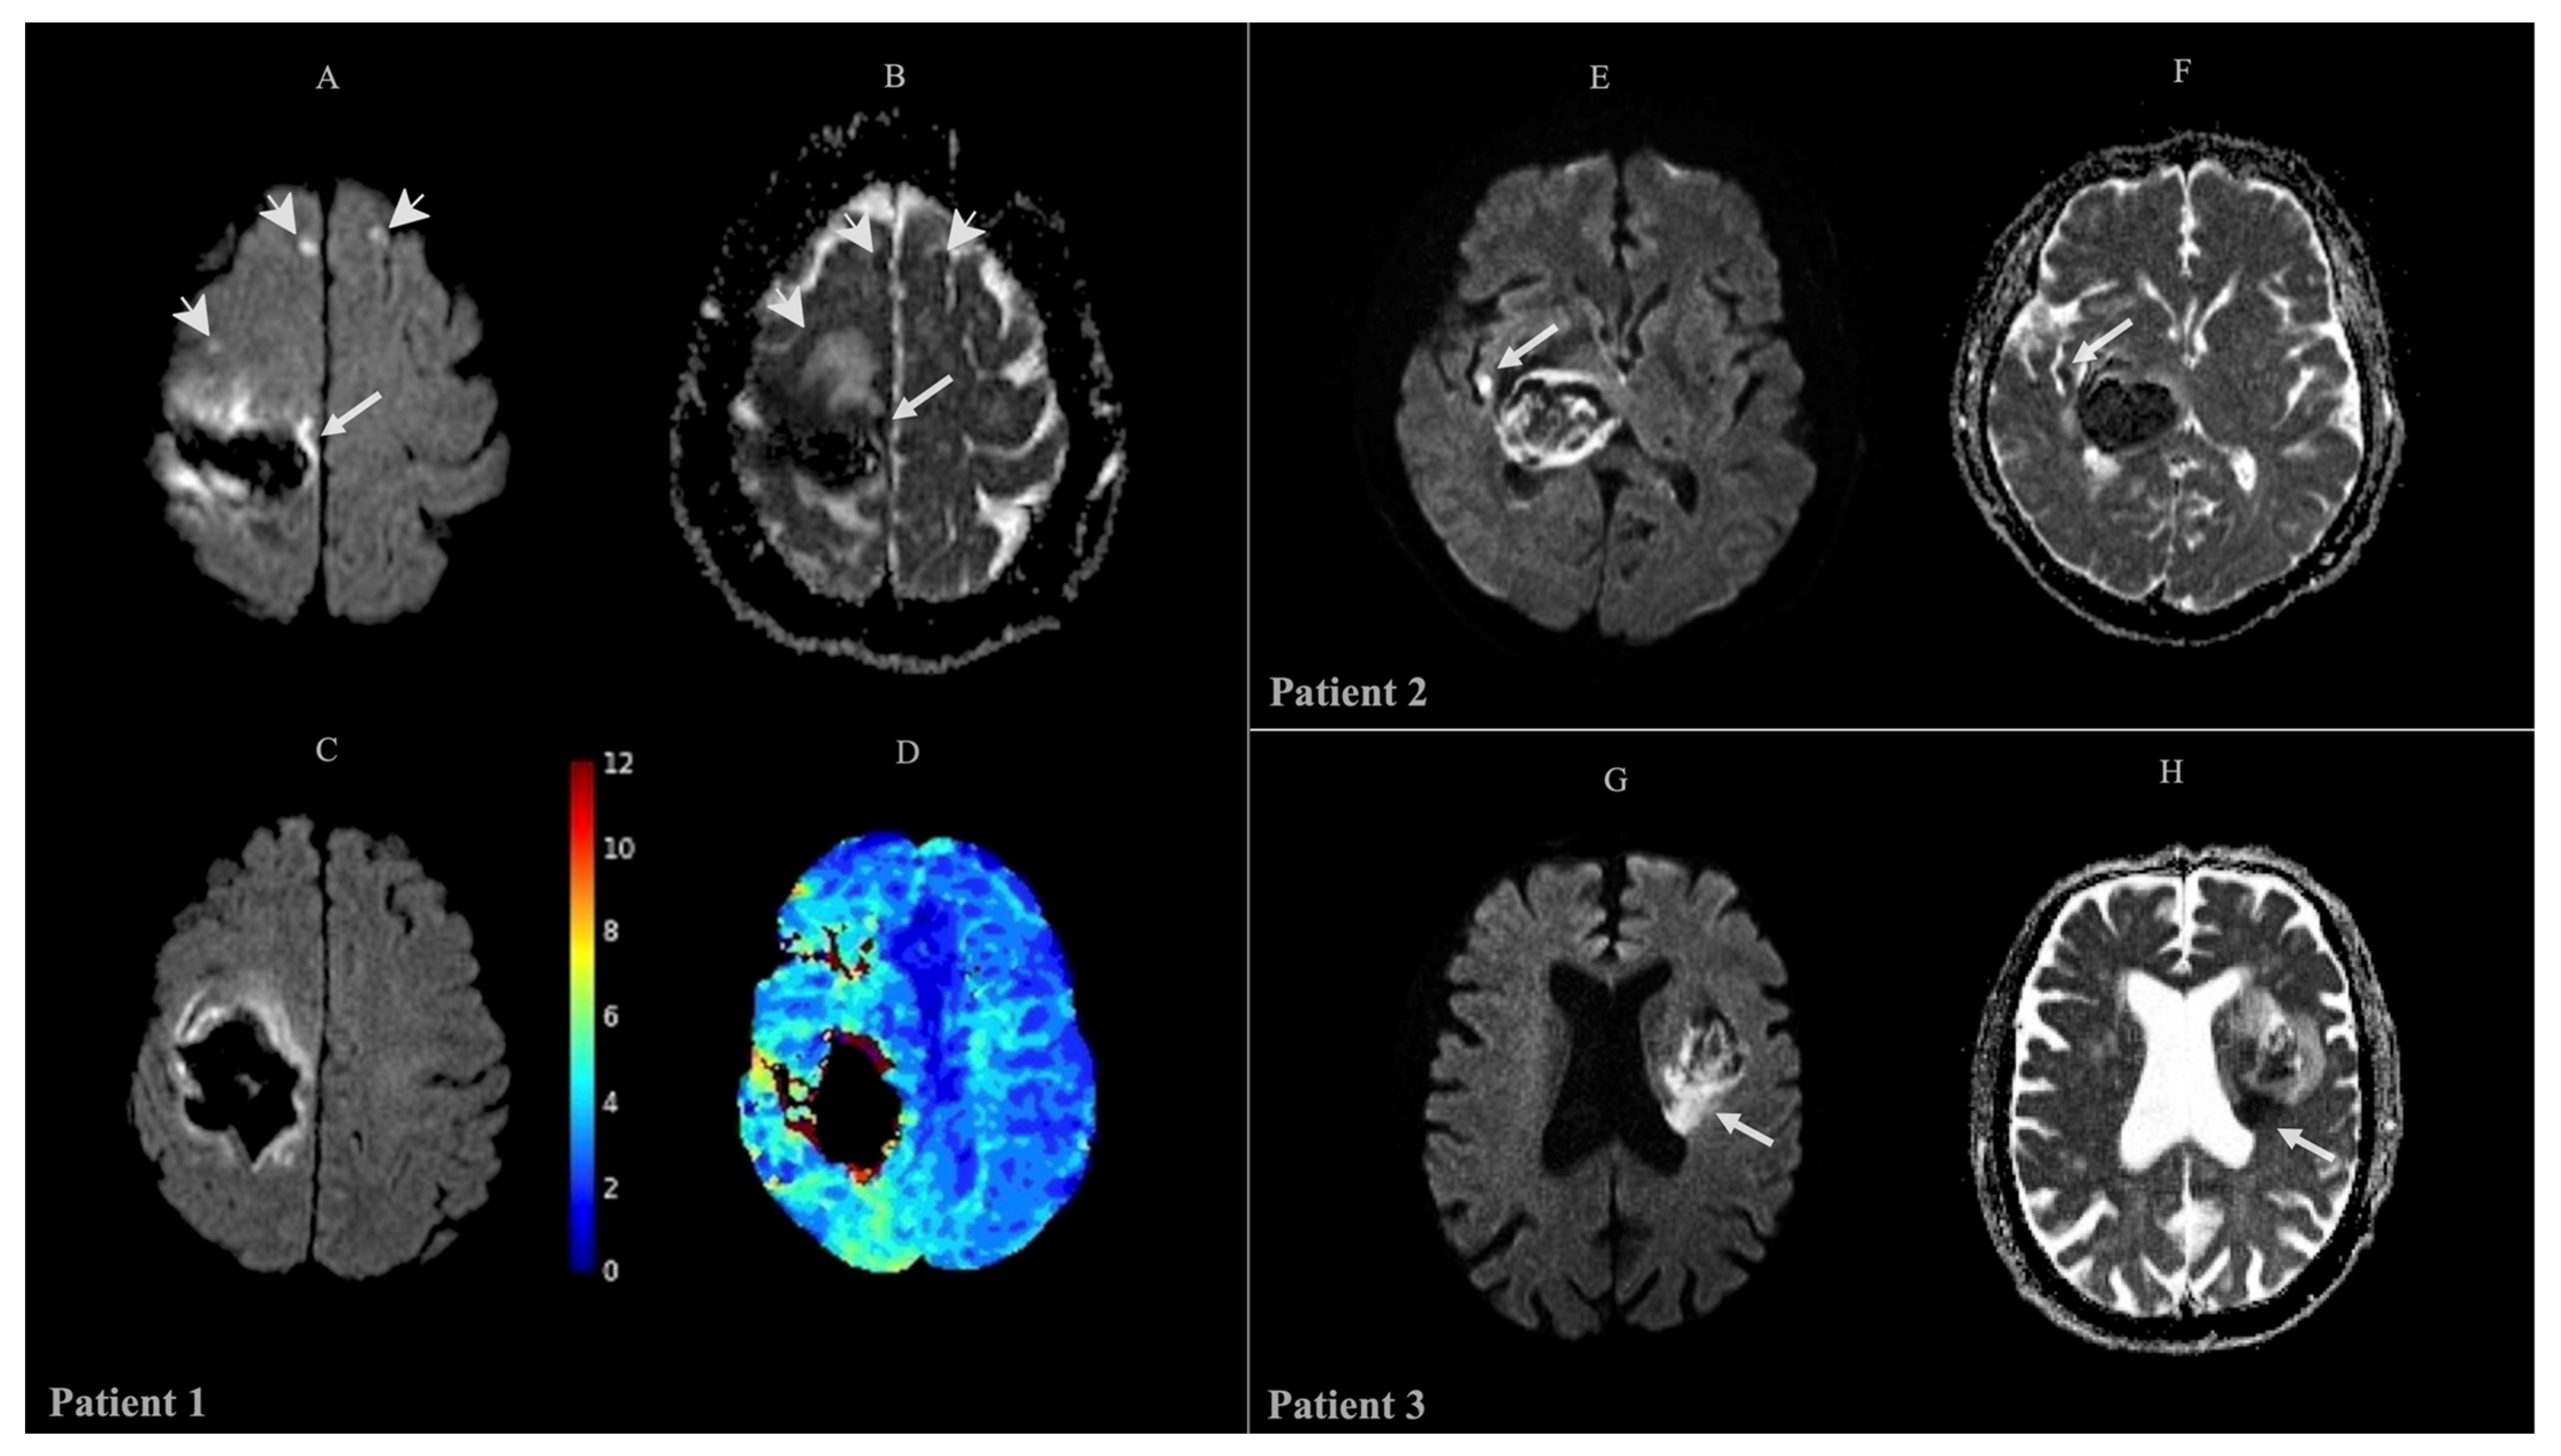

2.2. Radiological Features